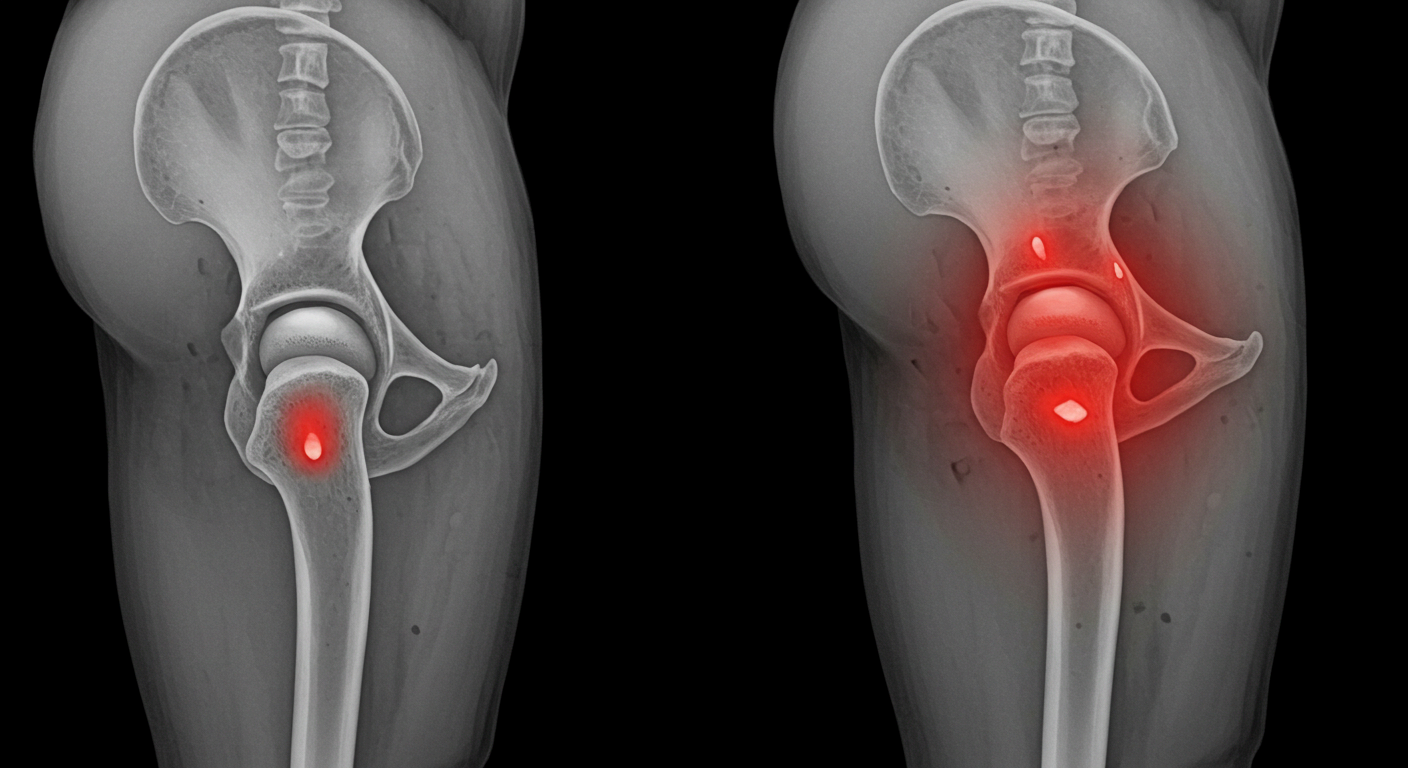

📌 대퇴골두 무혈성 괴사

- 혈액 공급 부족으로 뼈 조직이 괴사되어 통증 유발

- 음주, 스테로이드 과다 사용 등도 원인이 될 수 있음

📌 고관절 이형성증

- 선천적으로 고관절의 형성이 불완전하여 관절 불안정과 통증 유발

- 유아기에 진단되는 경우도 많고, 성인기에 퇴행성 질환으로 이어질 수 있음

3. 근육 및 신경성 요인

📌 둔근(엉덩이 근육) 약화

- 엉덩이 근육이 약하면 고관절이 제대로 지지되지 않아 통증 발생

📌 요추-골반 불균형

- 허리디스크나 척추측만증이 있는 경우 고관절에도 영향을 미침

- 골반이 기울어지면 한쪽 고관절에 무리가 집중되어 통증 유발

📌 좌골신경 압박

- 엉덩이나 허벅지 뒤쪽으로 퍼지는 저림 또는 통증이 있다면

고관절보다는 신경성 통증일 수 있으며, 좌골신경통과 감별이 필요합니다.